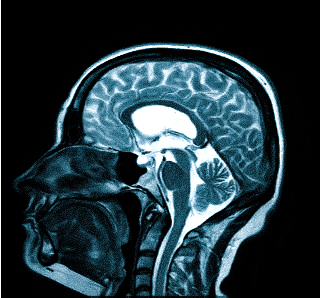

Выделяют несколько видов магнитно-резонансной томографии головы: нативную, усиленную контрастным препаратом и сканирование в ангиорежиме. К каждому исследованию есть свои показания, поэтому ответить на вопрос: “Какую МРТ делать при головной боли?” — не всегда возможно. Врач выбирает нужный тип диагностики, опираясь на клиническую картину. В оценке опухолевых новообразований и для определения стадийности (в том числе — метастатического распространения) используют МРТ с контрастированием. Введение препаратов на основе хелатов гадолиния позволяет рассмотреть даже небольшие опухоли в труднодоступных местах, поэтому магнитное сканирование с усилением с успехом применяют, если прочие способы визуализации показали неоднозначные результаты. При подозрении на сосудистое заболевание головного мозга оптимальным выбором будет проведение сканирования в ангиорежиме.

Необъяснимая цефалгия, возникающая регулярно и ухудшающая качество жизни не есть норма. Сильная боль -веский повод сделать МРТ головного мозга и не заниматься самолечением